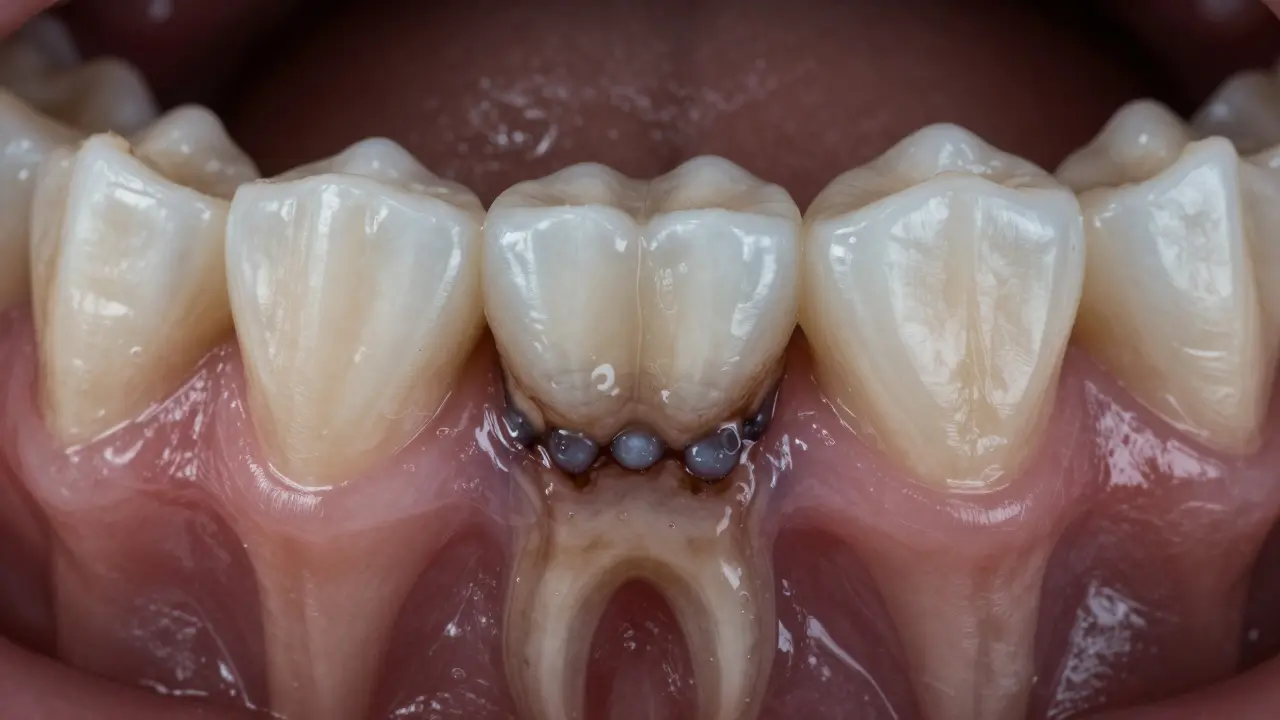

Na rozdíl od viditelného kamene na povrchu zubů, který může být žlutý nebo hnědý, kámen pod dásní je často tmavě černý nebo šedý. Je těžký, jak kámen, a přilnul k povrchu zubu tak pevně, že ho kartáček ani nit nemůže odstranit. A právě tady začíná problém - když se kámen tvoří pod dásní, nejenže dráždí tkáně, ale i způsobuje, že se dásně odtrhávají od zubu a vznikají tzv. parodontální kapsy.

Stomatolog měří hloubku parodontální kapsy pomocí sondy při rentgenovém snímku.

Nemůžete to zjistit sami. Kartáček, nit nebo ústní voda to neodhalí. Pouze stomatolog může pomocí speciálního měřidla (tzv. parodontálního sondu) změřit hloubku kaps mezi zubem a dásní. Normální hloubka je 1-3 mm. Pokud je více než 4 mm, znamená to, že se tam hromadí kámen a bakterie.

Kromě toho se provádí rentgen. Na snímku je vidět, jak moc se ztrácí kost kolem zubu. Pokud máte kámen pod dásní, rentgen ukáže jasný „výřez“ kolem kořene zubu.